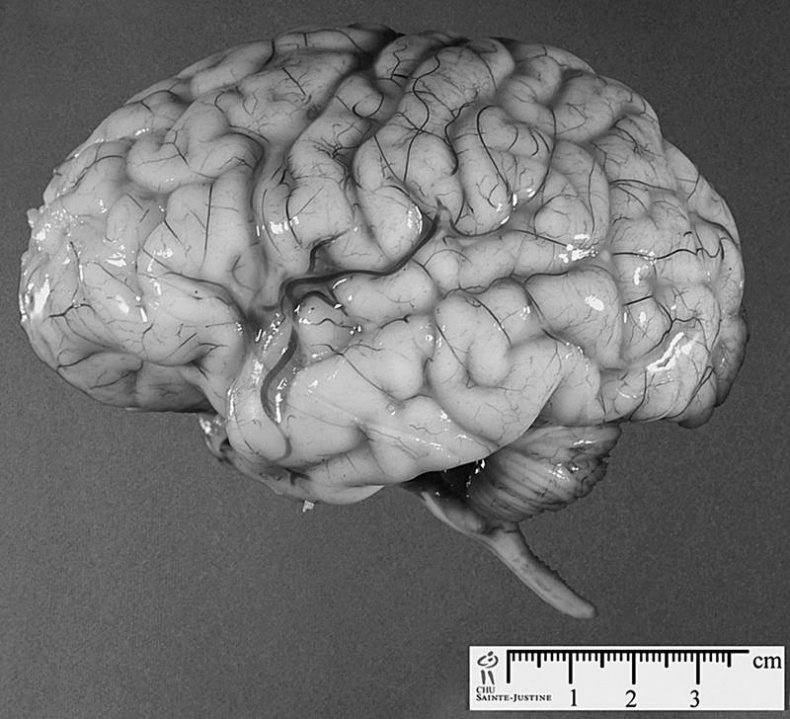

Иллюстрация к книге — 100 великих тайн сознания [i_005.jpg]

Мозг мужчины отличается от мозга женщины

Немало различий нашли исследователи и в строении мозга мужчин и женщин. Так, мозг мужчины на 150–200 граммов тяжелее женского.

Зато у женщин на 15–20 % серого вещества мозга, то есть нейронов, больше, чем у мужчин. Этот факт как раз и объясняет, почему у женщин, при меньшей массе их мозга, коэффициент интеллекта почти такой же, как и у мужчин. Просто мозг женщины в меньшем объеме содержит больше активных элементов.

А вот белого вещества, или глии, и внутримозговой жидкости в мозге мужчин больше, чем в мозге прекрасной половины. Именно глия, состоящая из покрытых изолирующей жировой оболочкой длинных отростков нейронов, позволяет четче распределять поступающую информацию между разными отделами мозга.

Правда, прямой и четкой связи между весом мозга, объемом серого вещества и глии и интеллектом мужчин и женщин не обнаружено.